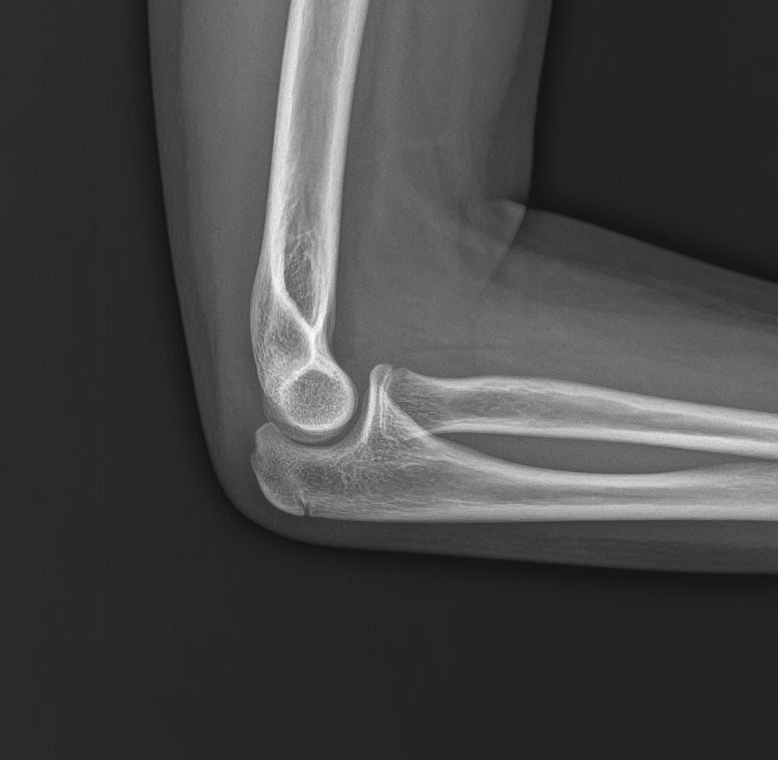

뼈나이는 어떨까요?

qqr.png

qr.png

실제 나이보다 1년 정도 앞서가고 있습니다. 처음 성조숙증 억제주사를 시작하기 전 2년 정도 앞서가 있던 것을 생각하면, 어느 정도 잘 조절된 것을 알 수 있습니다.